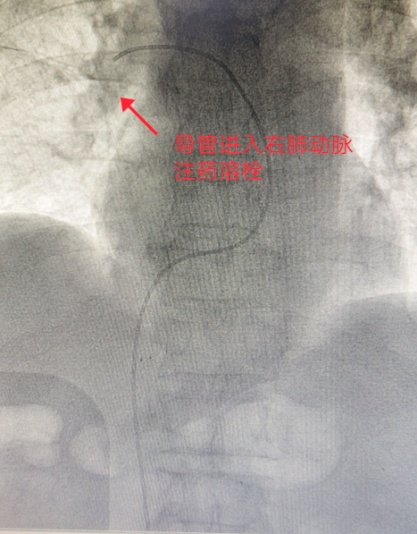

导管进入右肺动脉注药溶栓

考虑到老刘左下肢深静脉血栓持续形成且仍有脱落加重肺栓塞的风险,胡博士首先穿刺右侧股静脉放置下腔静脉滤器,拦截血栓。再经过穿刺的小口用导丝带导管进入肺动脉进行溶栓治疗。

溶栓过程中老刘的胸闷和呼吸急促症状逐渐缓解,心率由115次/分下降至85次/分。指脉氧由85%上升至93%。术后立即送到综合ICU进行高浓度氧疗。经过肺部CTA复查,老刘右肺动脉主干血栓溶解了大部分,基本通畅,左肺动脉血栓溶解了大部分。胡博士从死神手里帮老刘救回了一条命,老刘和家人都非常感谢医护人员。